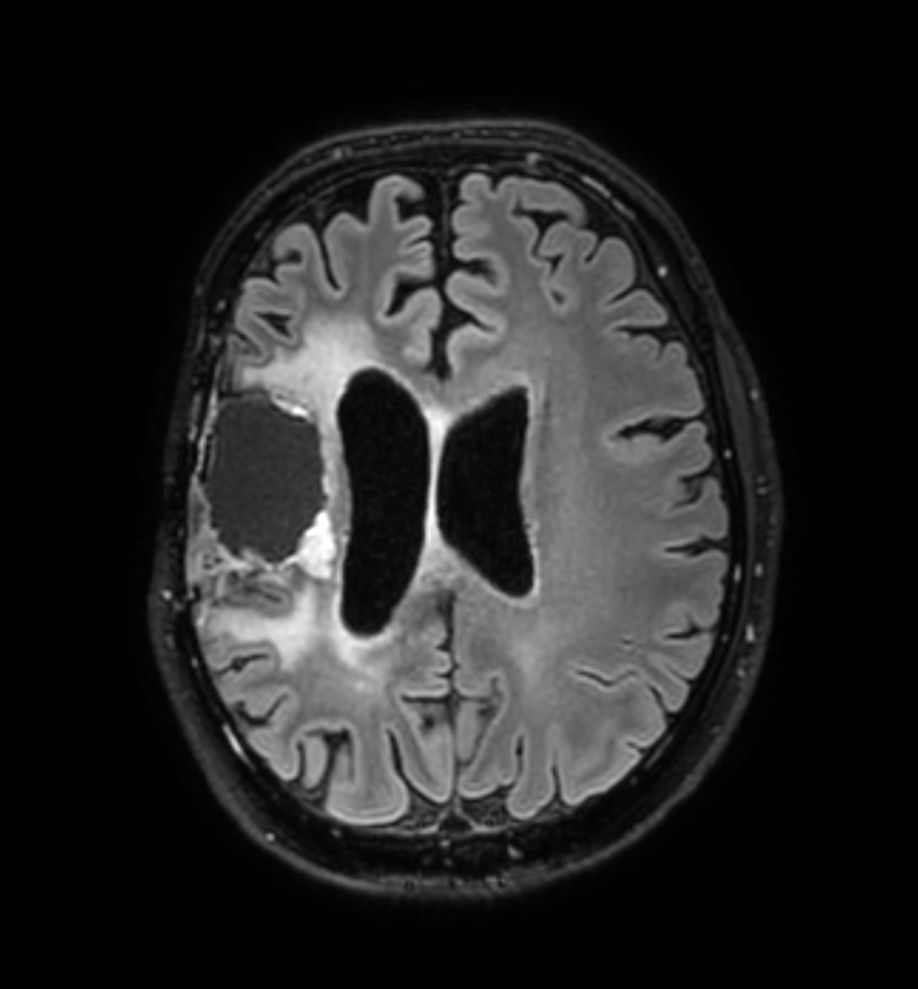

Brain glioblastoma, post-operative

Patient who was operated on glioblastoma

Axial T2w TSE

-